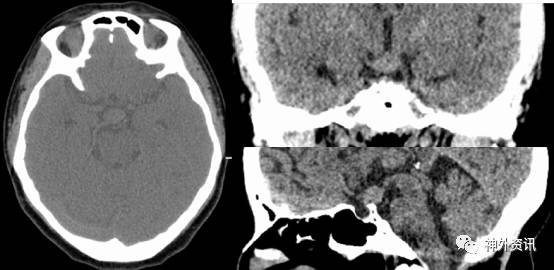

术后患者一般情况良好,意识清,无尿崩。复查头颅MRI示鞍上肿瘤部分残留,余无殊(图3)。至术后6天,患者出现精神症状,表现为烦躁,电解质、尿量、体温基本平稳,对症处理后恢复良好,于术后13天顺利出院。

图3. 术后MRI检查,提示肿瘤部分残留。